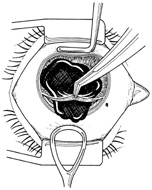

With lens removal, attention should first be paid to any prolapsed or incarcerated tissue. This should be repositioned or excised, and the corneal laceration should be sutured and the anterior chamber re-formed as described. The nature of the injury will suggest the surgical technique used for lens removal. If the lens capsule remains intact, standard phacoemulsification or extracapsular cataract extraction may be performed, making every effort to preserve the integrity of the posterior capsule. In children and young adults, a soft cataractous lens may be removed through a small incision using manual or automated aspiration. When extracting the nucleus in the patient post-trauma, one should be aware of the possibility of poor zonular support. Should zonular weakness, dialysis, or loss be present, a capsular tension ring (CTR) may be used. Implanting a CTR may decrease intraoperative zonule dehiscence, subluxation of the capsular bag, and posterior capsular rupture. A CTR inserted before phacoemulsification will permit support of the capsular bag, reestablishing its contour and protecting it from getting aspirated.14 The CTR (Morcher; distributed by FCI Ophthalmics, Inc., Marshfield Hills, MA) comes in three sizes and is usually inserted after capsulorrhexis and hydrodissection. For insertion, it is best to enter the bag in the area of greatest zonular weakness, thus placing stress on the stronger zonules, 180 degrees away. The ring is dialed into the bag using a second instrument (e.g., Y-hook) (Fig. 14). Alternatively, a CTR injector may be used.